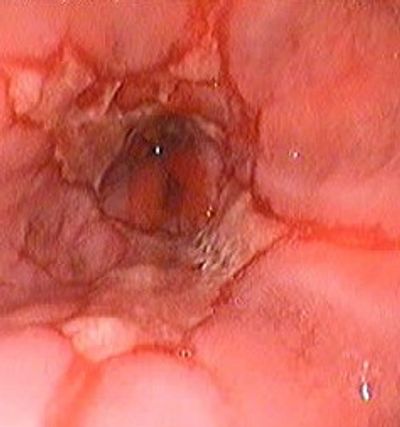

Gastroözofageal Reflü Hastalığı (GER) mide içeriğinin yemek borusuna (özofagus) geri kaçışına bağlı olarak ortaya çıkan ve yemek borusunda mukozal hasara neden olan kronik bir hastalıktır.

Tedavi edilmemesi durumunda özofajit (iltihap), özofagusta striktür (darlık), Barret özofagus (özofagus epitelinin mide asidi ve safra reflüsü sonucunda meydana gelen hasar sonrası kolumnar epitelle yer değiştirmesi), akciğer aspirasyonu ve buna bağlı pulmoner fibrozis gelişmektedir.

Uzayan hastalık yemek borusu kanseri gelişimi ile sonuçlanabilir.